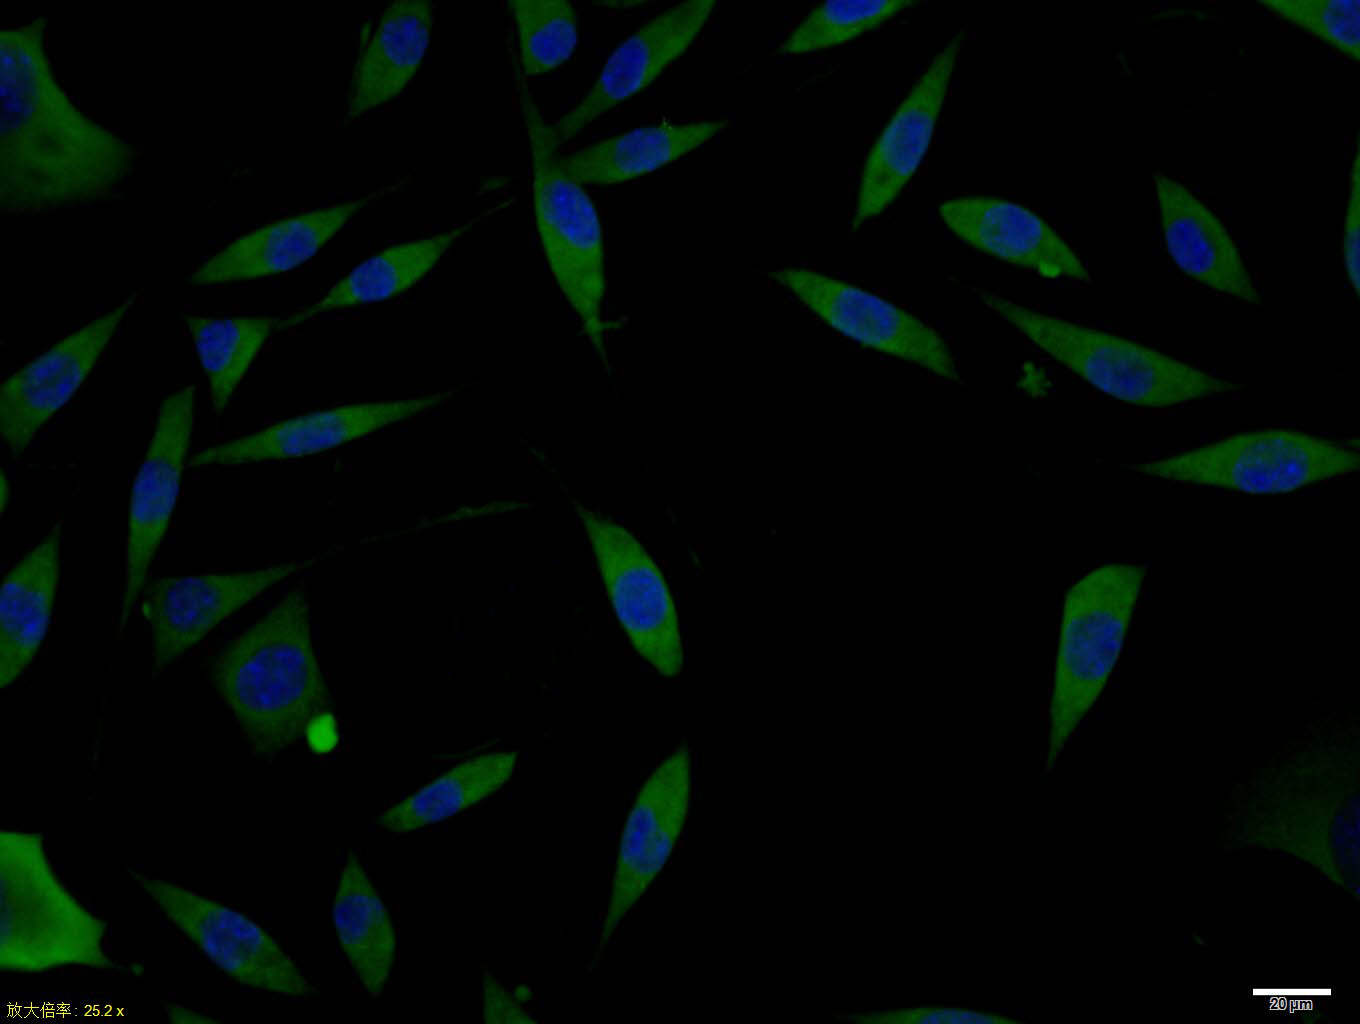

| 英文名称 | DCX/Doublecortin Rabbit pAb |

| 中文名称 | 双皮质素抗体 |

| 产品应用 | WB=1:500-2000, ICC/IF=1:100-500 Not yet tested in other applications. |

| 背景资料 | Neuronal Marker Doublecortin (DCX) is a microtubule-associated protein expressed almost exclusively in immature neurons. Neuronal precursors begin to express DCX shortly after exiting the cell cycle, and continue to express DCX for 2-3 weeks as the cells mature into neurons. Downregulation of DCX begins after 2 weeks, and occurs at the same time that these cells begin to express, a marker for mature neurons. Due to the nearly exclusive expression of DCX in developing neurons, this protein has been used increasingly as a marker for neurogenesis. Indeed, the levels of DCX expression increase in response to exercise, which occurs in parallel with increased BrdU labelling, currently a "gold standard" in measuring neurogenesis. |

| {ICC/IF} | {1:100-500} |